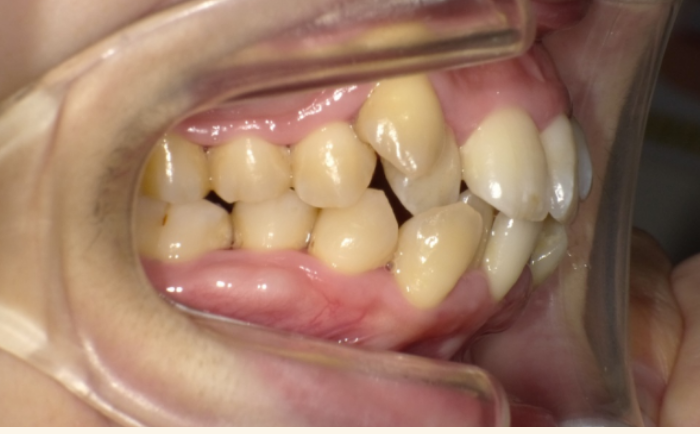

出っ歯・受け口など、噛み合わせ全体に問題があるケース

前歯の見た目だけでなく、「上の歯だけ大きく前に出ている」「下の歯が前に出ている」「前歯が浮いていて噛み合っていない」など、噛み合わせそのものに問題がある場合です。 このタイプを前歯だけで動かそうとすると、一時的に見た目が良くなっても、奥歯の噛み合わせがずれてしまい、将来の噛みにくさや顎の負担につながることがあります。そのため、上下の噛み合わせごとしっかり整える「全体矯正」が向いていることが多いです。